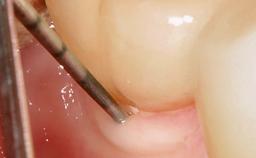

Peri-Implantitis Modified by the Presence of Submucosal Excess Cement: Reconstructive Therapy and a Ten-Year Follow-up

This case outlines the reconstructive therapy by Giovanni Salvi resulting in defect fill and inflammation-free peri-implant soft tissues at 10-year follow up. This case highlights the importance of regular monitoring of implants during supportive therapy.